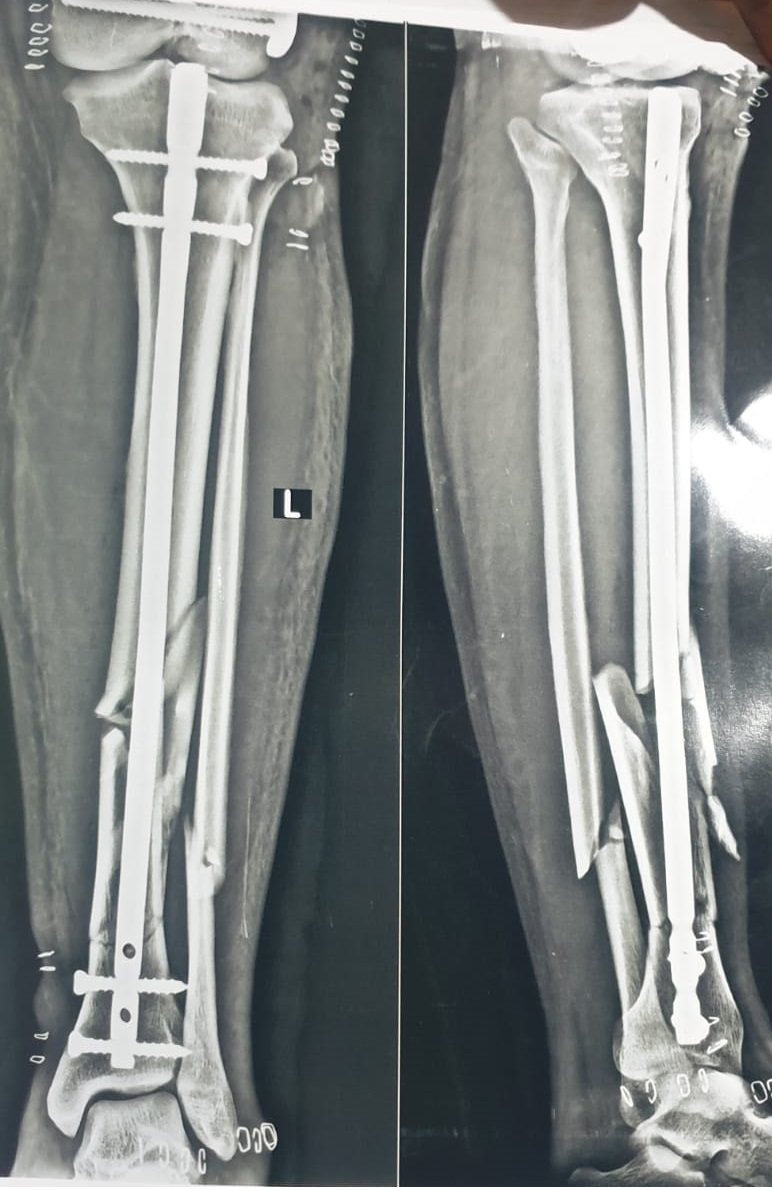

A Successful Case Study: Expert Tibia Nailing for Diaphyseal Segment Fragmentary Fracture

Radiological evaluation revealed multiple fracture segments in the midshaft region with loss of structural continuity. The Samay Surgical Pvt. Ltd.’s Expert Tibia Nail was chosen for its high mechanical strength and ability to support complex shaft injuries effectively.

Surgical Procedure:

A precise entry point was created at the proximal tibia, and a guidewire was advanced under fluoroscopy. After preparing the canal, Samay Surgical Pvt. Ltd.’s Expert Tibia Nail was inserted to realign and stabilize all fracture segments. Proximal and distal locking screws secured the construct, restoring length and rotational control. Final imaging confirmed perfect positioning, and the incision was closed, completing a smooth and efficient procedure.

The patient was monitored for swelling, pain, and circulation, with early physiotherapy started to maintain joint movement. Weight-bearing was introduced in stages as healing progressed and X-rays confirmed stable fixation around the Expert Tibia Nail. Overall recovery remained smooth, with steady improvements in mobility and comfort.

The patient achieved excellent fracture stability and alignment, supported by the reliability of Samay Surgical’s Expert Tibia Nail system. Rapid functional improvement and smooth rehabilitation reflected the strength and precision of Samay Surgical’s orthopedic solutions.